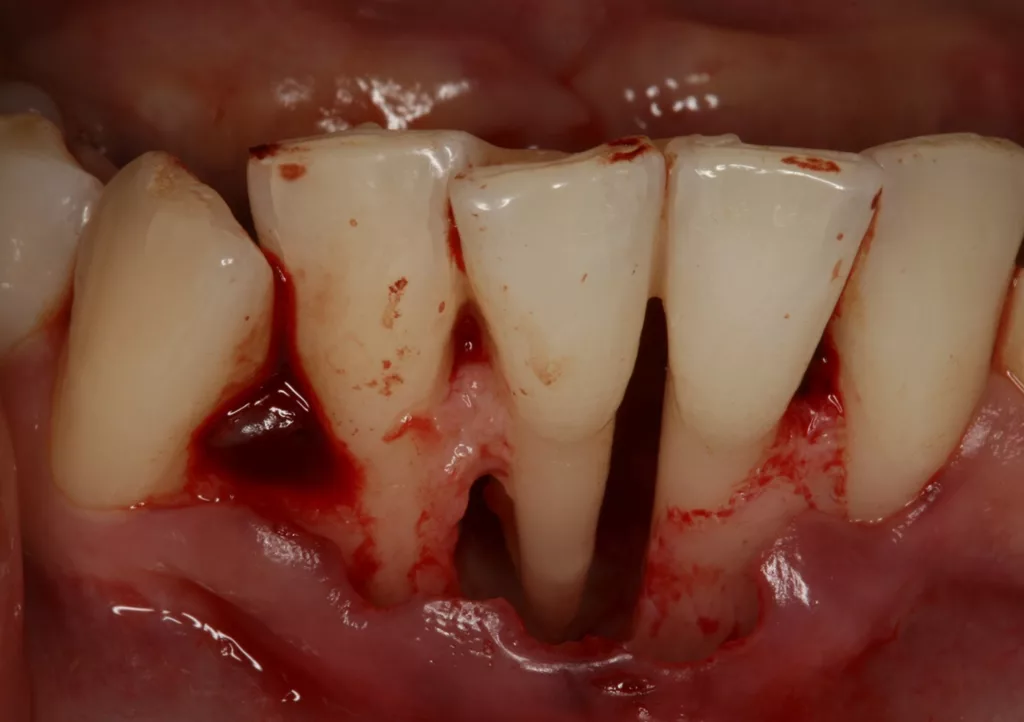

Wir sind vor mittlerweile 17 Jahren erstmals mit der Frage etwaiger Auswirkungen oraler Piercings auf den Zahnhalteapparat konfrontiert worden [10]. Eine damals 24-jährige Patientin stellte sich mit einem ungewöhnlichen Befund vor (Abb. 3a bis d). Bei sonst parodontal unauffälligen Verhältnissen mit Sondierungstiefen zwischen 2 und 3 mm, reichten die Sondierungstiefen an den Schneidezähnen im Unterkiefer bis 12 mm. Zahn 41 schmerzte und wies eine erhöhte Lockerung von Grad 2 auf. Bukkal war zudem eine Fistel mit Pusentleerung zu detektieren. Die Patientin war allgemeinmedizinisch gesund, rauchte nicht und hatte auch keinen Diabetes mellitus. Eine familiäre Prädisposition für parodontale Erkrankungen ließ sich anamnestisch nicht konstruieren. Die Mundhygiene war zwar nicht perfekt, stand aber auch in keinem Verhältnis zu ihrem dramatischen lokalen parodontalen Befund. Im Rahmen der anamnestischen Befragung, fokussiert auf ungewöhnliche Habits, berichtete die Patientin, bis vor kurzem ein Zungenpiercing getragen zu haben, dieses aber vor ca. sechs Monaten entfernt zu haben. Die Piercing-Tragedauer betrug etwa drei Jahre.

In der Gesamtschau der zusammengetragenen Daten und unter Berücksichtigung der in medizinischen Datenbanken aufgefundenen einzelnen Fallbeschreibungen erschien uns die wahrscheinlichste Ursache für den vorliegenden Befund tatsächlich das Zungenpiercing zu sein [11]. Die parodontale nicht-chirurgische, wie auch die chirurgisch-regenerative Therapie waren nicht erfolgreich und die Patientin verlor den stark kompromittierten Unterkiefer-Frontzahn. Seit dieser Zeit beschäftigen wir uns intensiver mit diesem Thema. So begannen wir mit der Sammlung und Erfassung der klinischen Parameter bei Patienten/-innen, die ein orales Piercing tragen oder einst trugen. Die Ergebnisse wurden zunächst im Rahmen einer Masterarbeit ausgewertet, als Posterbeitrag bei der Europerio 9 in Amsterdam veröffentlicht und später dann als Manuskript publiziert [10,12].

Die hier diskutierte Symptomatik lokaler parodontaler Destruktion ähnelt einem bekannten Krankheitsbild, zuletzt neu bezeichnet in der letzten Klassifikation parodontaler und peri-implantärer Erkrankungen und Zustände [15]. Konkret eine endo-parodontale Läsion mit einer Beschädigung der Wurzel, durch eine Fraktur oder einen Riss, eine Perforation oder eine externe Wurzelresorption. Eine lokal erhöhte Sondierungstiefe in einem sonst parodontal eher unauffälligen Gebiss dient hier als Alarmsignal für ein derartiges Krankheitsbild, welches weitere Diagnostik, wie z.B. eine Vitalitätsprobe oder radiologische Aufnahmen, nach sich zieht. In vielen Fällen sind diese konservativen nicht-invasiven Techniken aber nicht in der Lage, eine Fraktur sicher auszuschließen. Oft ist dann ein explorativer parodontal-chirurgischer Eingriff mit Darstellung und Anfärben der Wurzel zur Detektion etwaiger Frakturen/Risse das Mittel der Wahl. Eine Wurzelfraktur oder auch nur ein schmaler Riss, hervorgerufen durch das konstante, oft mehrjährige mechanische Trauma durch ein Zungenpiercing, könnte eine Erklärung für die lokale parodontale Destruktion an den grazilen Unterkiefer-Frontzähnen sein.

![Abb. 3a: Klinische Dokumentation einer 24-jährigen Patientin mit einer weit fortgeschrittenen lokalen parodontalen Destruktion, die mit großer Wahrscheinlichkeit durch ein Zungenpiercing hervorgerufen wurde [10]. Mit Ausnahme der Symptomatik im Unterkiefer-Frontzahnbereich wies die Patientin flache Sondierungstiefen und einzelne Regionen mit Gingivitis auf. Die Zähne reagierten positiv auf eine Sensibilitätsprobe mit Kältespray. Das Piercing war zum Zeitpunkt der Vorstellung in der Klinik bereits nicht mehr im Mund. Es wurde eine stufenweise systematische parodontale Therapie eingeleitet. Die verbliebenen und nahezu unveränderten erhöhten Son¬dierungstiefen wurden einem parodontal-chirurgischen Eingriff mit zusätzlichen, die Regenera¬tion fördernden Maßnahmen (Straumann Emdogain, Straumann, Basel, Schweiz) unterzogen. Es wurde die für diese Operationen empfohlene Schnittführung im Sinne eines Papillenerhaltungs¬lappens angewendet. Der nach der Degranulierung mit Hand- und Ultraschallinstrumenten sicht¬bare knöcherne Defekt wies eine ungünstige Morphologie für die Regeneration auf. Ein primärer Wundverschluss wurde dennoch erzielt. Diese Ansätze blieben letztendlich erfolglos und der Zahn 41 ging verloren (parodontologische Therapie gemeinsam mit Dr. L. Büttel, Basel, Schweiz).](https://dentalwelt.spitta.de/wp-content/uploads/2025/07/Abb-3a-1024x684.webp)

![Abb. 3b: Klinische Dokumentation einer 24-jährigen Patientin mit einer weit fortgeschrittenen lokalen parodontalen Destruktion, die mit großer Wahrscheinlichkeit durch ein Zungenpiercing hervorgerufen wurde [10]. Mit Ausnahme der Symptomatik im Unterkiefer-Frontzahnbereich wies die Patientin flache Sondierungstiefen und einzelne Regionen mit Gingivitis auf. Die Zähne reagierten positiv auf eine Sensibilitätsprobe mit Kältespray. Das Piercing war zum Zeitpunkt der Vorstellung in der Klinik bereits nicht mehr im Mund. Es wurde eine stufenweise systematische parodontale Therapie eingeleitet. Die verbliebenen und nahezu unveränderten erhöhten Son¬dierungstiefen wurden einem parodontal-chirurgischen Eingriff mit zusätzlichen, die Regenera¬tion fördernden Maßnahmen (Straumann Emdogain, Straumann, Basel, Schweiz) unterzogen. Es wurde die für diese Operationen empfohlene Schnittführung im Sinne eines Papillenerhaltungs¬lappens angewendet. Der nach der Degranulierung mit Hand- und Ultraschallinstrumenten sicht¬bare knöcherne Defekt wies eine ungünstige Morphologie für die Regeneration auf. Ein primärer Wundverschluss wurde dennoch erzielt. Diese Ansätze blieben letztendlich erfolglos und der Zahn 41 ging verloren (parodontologische Therapie gemeinsam mit Dr. L. Büttel, Basel, Schweiz).](https://dentalwelt.spitta.de/wp-content/uploads/2025/07/Abb-3b-1024x684.webp)

![Abb. 3c: Klinische Dokumentation einer 24-jährigen Patientin mit einer weit fortgeschrittenen lokalen parodontalen Destruktion, die mit großer Wahrscheinlichkeit durch ein Zungenpiercing hervorgerufen wurde [10]. Mit Ausnahme der Symptomatik im Unterkiefer-Frontzahnbereich wies die Patientin flache Sondierungstiefen und einzelne Regionen mit Gingivitis auf. Die Zähne reagierten positiv auf eine Sensibilitätsprobe mit Kältespray. Das Piercing war zum Zeitpunkt der Vorstellung in der Klinik bereits nicht mehr im Mund. Es wurde eine stufenweise systematische parodontale Therapie eingeleitet. Die verbliebenen und nahezu unveränderten erhöhten Son¬dierungstiefen wurden einem parodontal-chirurgischen Eingriff mit zusätzlichen, die Regenera¬tion fördernden Maßnahmen (Straumann Emdogain, Straumann, Basel, Schweiz) unterzogen. Es wurde die für diese Operationen empfohlene Schnittführung im Sinne eines Papillenerhaltungs¬lappens angewendet. Der nach der Degranulierung mit Hand- und Ultraschallinstrumenten sicht¬bare knöcherne Defekt wies eine ungünstige Morphologie für die Regeneration auf. Ein primärer Wundverschluss wurde dennoch erzielt. Diese Ansätze blieben letztendlich erfolglos und der Zahn 41 ging verloren (parodontologische Therapie gemeinsam mit Dr. L. Büttel, Basel, Schweiz).](https://dentalwelt.spitta.de/wp-content/uploads/2025/07/Abb-3c-1024x722.webp)

![Abb. 3d: Klinische Dokumentation einer 24-jährigen Patientin mit einer weit fortgeschrittenen lokalen parodontalen Destruktion, die mit großer Wahrscheinlichkeit durch ein Zungenpiercing hervorgerufen wurde [10]. Mit Ausnahme der Symptomatik im Unterkiefer-Frontzahnbereich wies die Patientin flache Sondierungstiefen und einzelne Regionen mit Gingivitis auf. Die Zähne reagierten positiv auf eine Sensibilitätsprobe mit Kältespray. Das Piercing war zum Zeitpunkt der Vorstellung in der Klinik bereits nicht mehr im Mund. Es wurde eine stufenweise systematische parodontale Therapie eingeleitet. Die verbliebenen und nahezu unveränderten erhöhten Son¬dierungstiefen wurden einem parodontal-chirurgischen Eingriff mit zusätzlichen, die Regenera¬tion fördernden Maßnahmen (Straumann Emdogain, Straumann, Basel, Schweiz) unterzogen. Es wurde die für diese Operationen empfohlene Schnittführung im Sinne eines Papillenerhaltungs¬lappens angewendet. Der nach der Degranulierung mit Hand- und Ultraschallinstrumenten sicht¬bare knöcherne Defekt wies eine ungünstige Morphologie für die Regeneration auf. Ein primärer Wundverschluss wurde dennoch erzielt. Diese Ansätze blieben letztendlich erfolglos und der Zahn 41 ging verloren (parodontologische Therapie gemeinsam mit Dr. L. Büttel, Basel, Schweiz).](https://dentalwelt.spitta.de/wp-content/uploads/2025/07/Abb-3d-1024x665.webp)